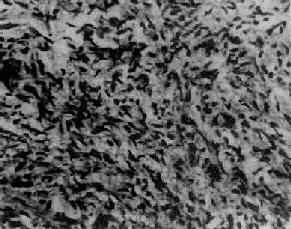

(2)鏡下特點:生殖細胞巢,纖維間隔,淋巴細胞浸潤。瘤組織由成片、島狀或梁索狀分布的圓形或多角形大細胞構成,細胞直徑15~25µm,界限清楚。細胞核大而圓,核膜清楚,呈空泡狀,核仁明顯,核分裂象易見,嗜酸性。分化差的腫瘤細胞異型性明顯。間質由纖維結締組織和淋巴細胞構成,偶爾由具生髮中心的淋巴濾泡形成。有時觀察到由組織細胞和多核巨細胞構成的肉芽腫樣結節。